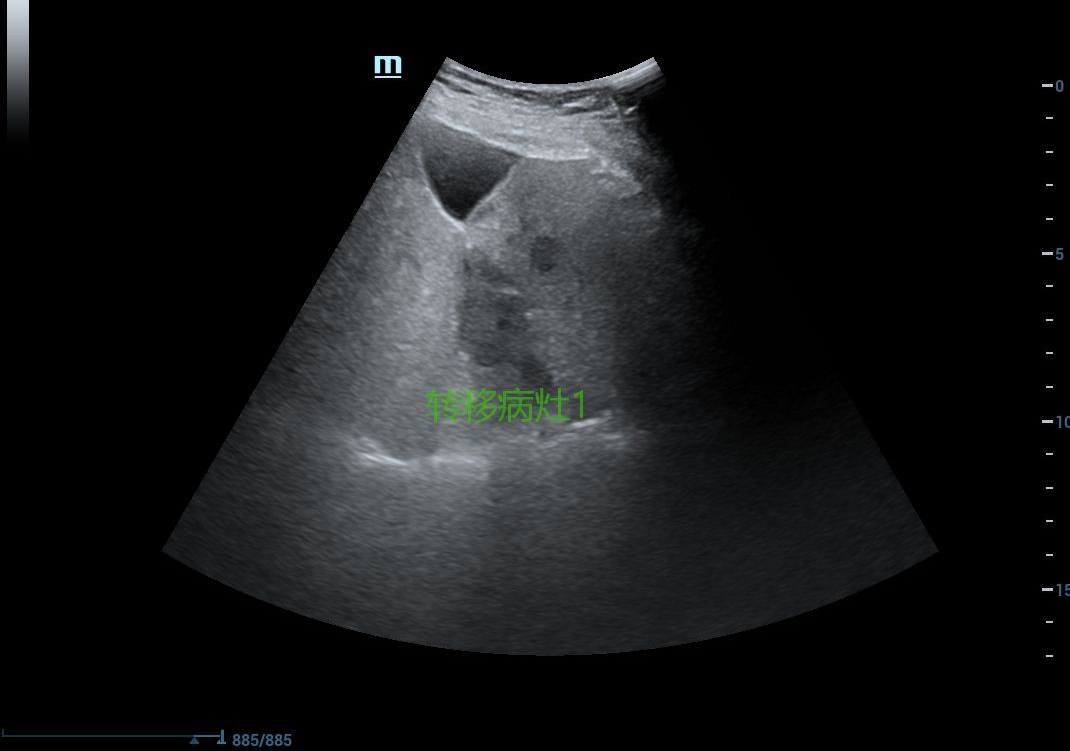

结肠癌肝转移患者多发转移病灶